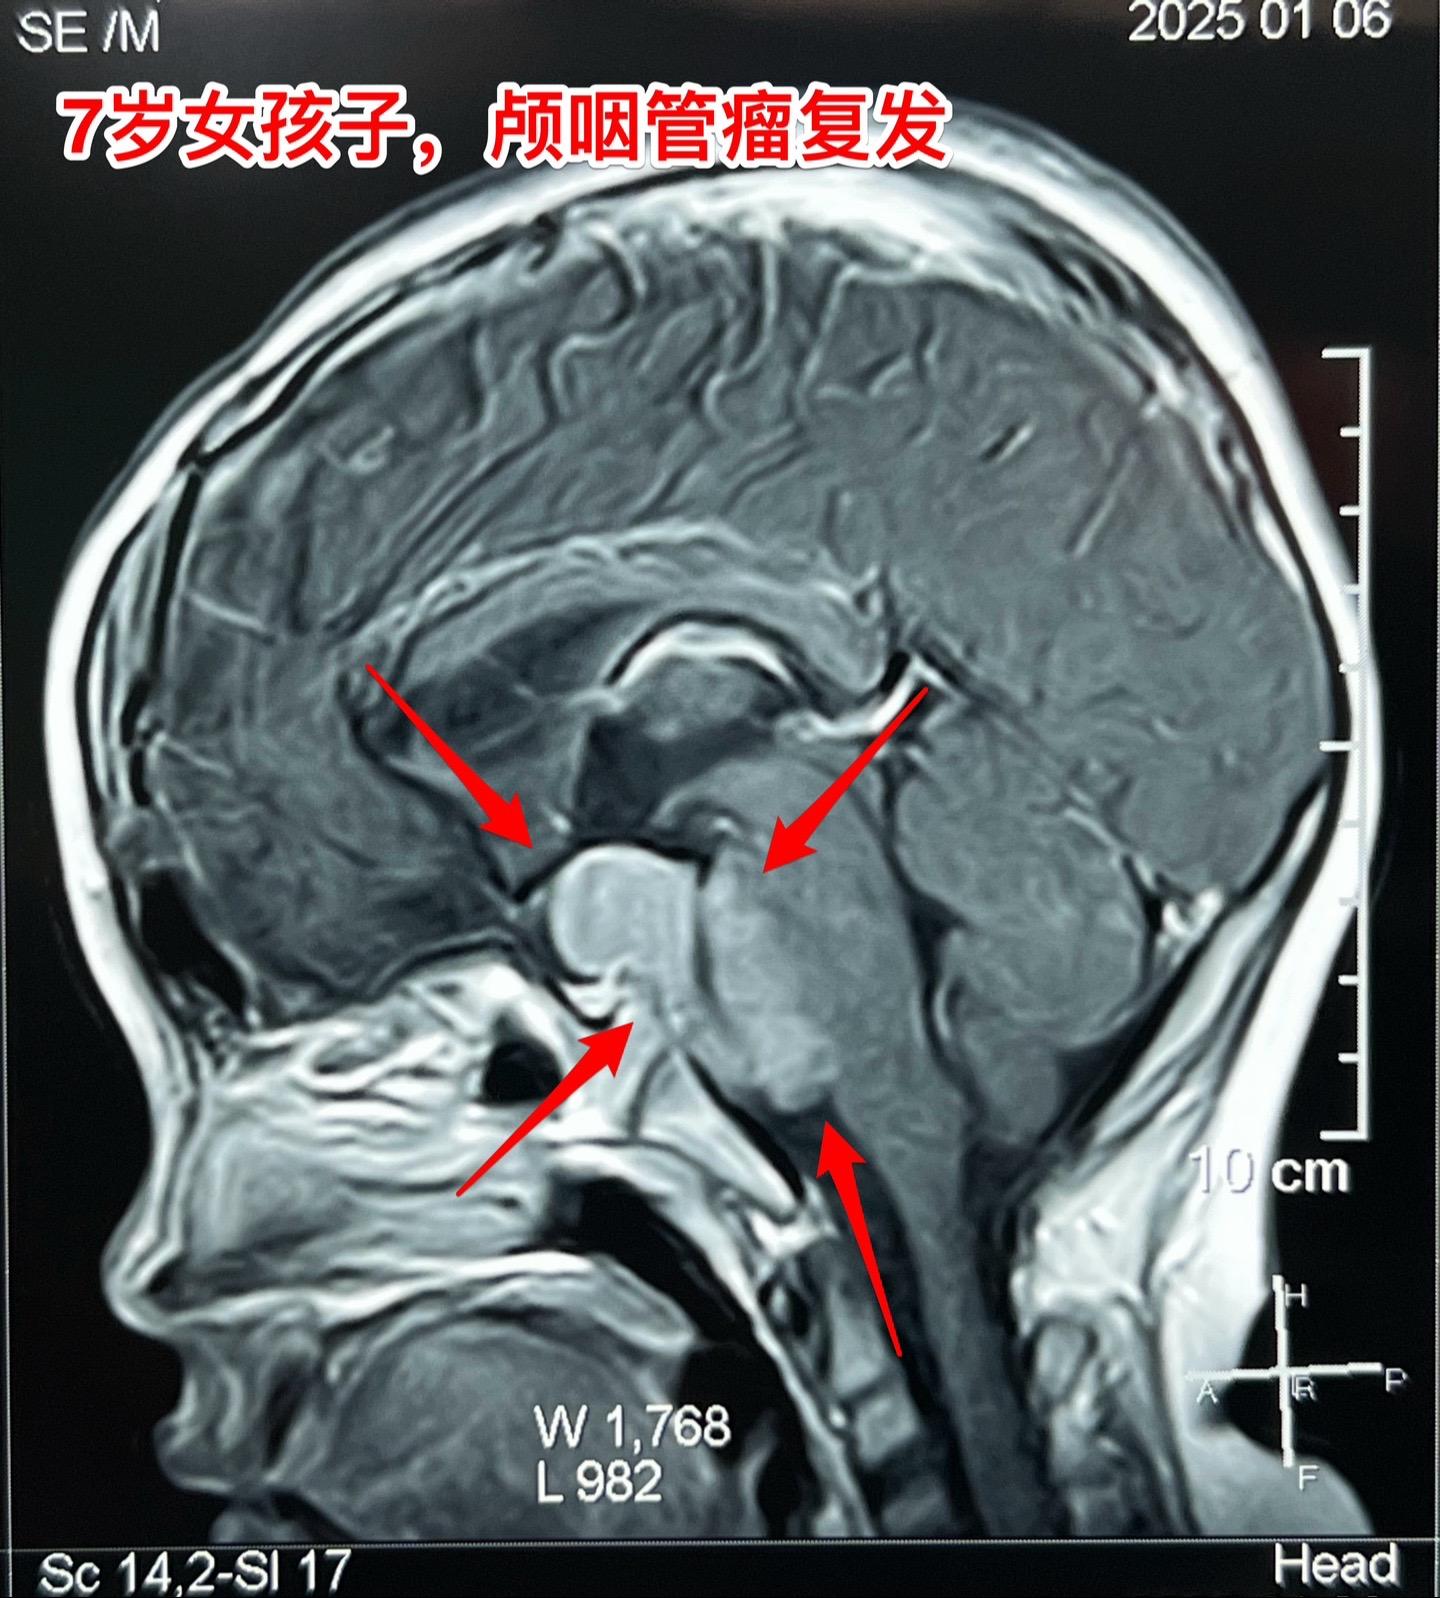

颅咽管瘤复发,看起来是一个瘤其实有三个。7岁女孩子,颅咽管瘤复发。从CT和磁共振来看,是一个大的囊性肿瘤,体积很大了,肿瘤向后颅窝生长,手术切除的难度还是比较大的。 2025年1月10日作手术过程中发现的情况比预想的还要复杂得多。除了这个大的囊性肿瘤之外还发现了两个孤立肿瘤。 这样的情况在我们科并不罕见,经常发现复发的颅咽管瘤病人脑部不止是一个瘤,有的时候有超过10个孤立的肿瘤。这种情况就要考验医生的技术和意志力了。当然,在我们科,总是争取把看见的瘤完全切除。